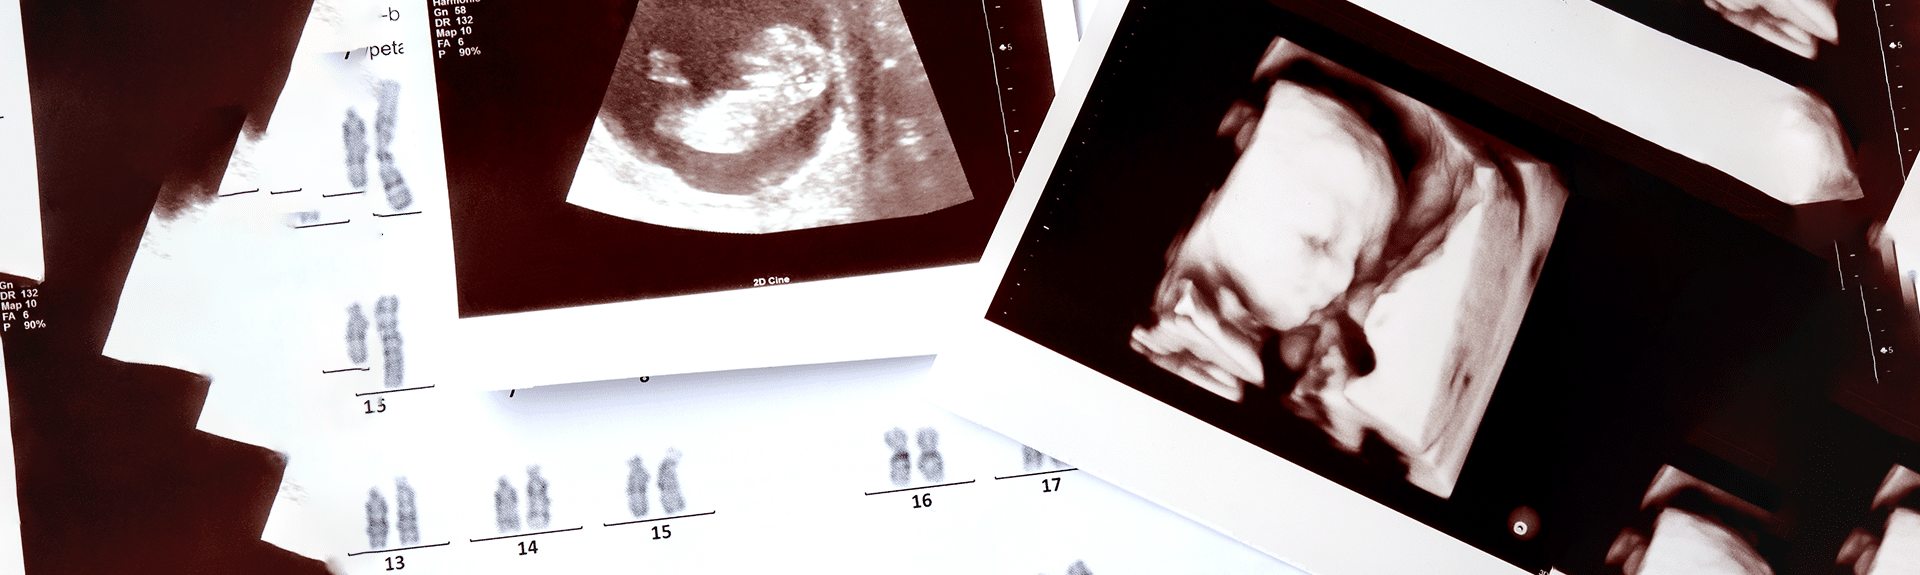

תסמונת דאון הינה מחלה תורשתית הנובעת מטריזומיה (פגם גנטי) בכרומוזום מספר 21 (ליתר דיוק – זה הוא מצב שבו  קיימים שלושה עותקים של הכרומוזום בכל התאים בגוף או בחלקם, במקום שני עותקים בלבד).

תסמונת דאון (Down Syndrome) היא התסמונת הגנטית השכיחה ביותר מבין כלל ההפרעות הכרומוזומליות. מדובר בליקוי גנטי הנגרם כתוצאה מהופעת שלושה עותקים של כרומוזום מספר 21 (במקום שניים) בכל תא בגוף- תופעה הידועה בשם "טריזומיה 21".

בדיקות אלו כוללות בדיקות דם פשוטות של האם (כגון תבחין משולש או תבחין משולב) ולעיתים שילוב עם אולטרסונוגרפיה (שקיפות עורפית). מטרתן להעריך את הסיכון להימצאות מומים גנטיים בעובר, לרבות תסמונת דאון.

בדיקות כגון דיקור מי שפיר או דגימת סיסי שליה מאפשרות קבלת מידע ודאי על מצבו הגנטי של העובר באמצעות בדיקה ישירה של הכרומוזומים בתאי השליה או מי השפיר. רמת הדיוק של בדיקות אלו היא כ-99%, אך הן כרוכות בסיכון מסוים להיריון (כגון סיכון להפלה).